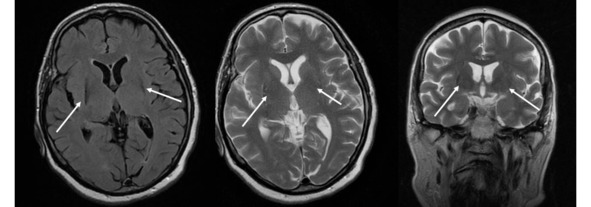

Несмотря на то что МРТ в стандартных режимах не выявляет каких-либо патогномоничных признаков при БП, этот метод позволяет исключить другие структурные поражения мозга, сопровождающиеся синдромом паркинсонизма. К таким патологиям относятся опухоль базальных ганглиев, нормотензивная гидроцефалия, сосудистые поражения, изменения сигнала от базальных ганглиев вследствие болезни Вильсона-Коновалова, отравления марганцем и др. МРТ помогает также в дифференциальной диагностике БП с паркинсонизмом вследствие нейродегенеративных заболеваний, при каждом из которых МРТ имеет ряд специфических симптомов: «глаза тигра» (рис. 14).

Рис. 14. Пример МР-томограмм пациентки 69 лет с «нейродегенерацией с отложением железа в мозге» (NBIA-Syndrom – Neurodegeneration with Brain Iron Accumulation). В проекции базальных ганглиев (отмечены стрелками) выявляются симметричные вытянутые зоны изменения МР-сигнала, неоднородного гипоинтенсивного МР-сигнала на Т2ВИ, Flair, изоинтенсивные на Т1 ВИ, что может соответствовать накоплению железа в базальных ганглиях.